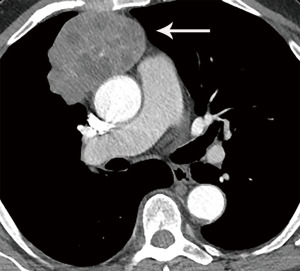

Computed tomography (CT) with contrast is the imaging modality of choice to evaluate thymic tumors due to its high spatial and temporal resolution, ease of access, and convenience. CT can reliably discern location, size/shape, morphology, margins, density, enhancement, and relationship to, or invasion of, adjacent structures (4) (Figure 2). Overall, CT is equal or superior to magnetic resonance imaging (MRI) in the evaluation of mediastinal masses with the caveat that MRI better evaluates thymic cysts or cystic components of tumors (5) (Figure 3).

The role of fluorodeoxyglucose (FDG) positron emission tomography (PET)/computed tomography (CT) in thymic mass evaluation is incompletely defined. False-positive studies can be seen with FDG uptake in non-neoplastic masses, such as in the setting of infection, thymic hyperplasia, or fibrosing mediastinitis. False-negative studies can be seen in certain histological types of thymic malignancy with lower metabolic activity. Additionally, there is lack of technique standardization which results in quantitative variability between studies (8). Given that other prevascular masses such as malignant germ cell tumor and lymphoma are often FDG avid, the presence of a hypermetabolic prevascular mass cannot distinguish between various tumors. There are studies that report that FDG uptake can help predict tumor invasiveness and prognosis. Other studies report FDG uptake as useful in differentiating low-grade from high-grade thymic malignancies; however, other studies report these observations as controversial due to overlapping imaging findings and FDG uptake between low-grade and high-grade thymic tumors (9). Overlapping findings are less common in more aggressive tumors, such as thymic carcinoma, due to higher overall tumor metabolism, with studies reporting that a maximum standard uptake value (SUVmax) of 6 can serve as a cutoff between thymic carcinoma and lower grade thymic tumors (10) (Figures 2,3). However, this threshold cannot differentiate thymic carcinoma from other malignancies such as lymphoma or non-seminomatous germ cell tumor. Finally, PET/CT clearly has a role to detect occult metastasis in hypermetabolic tumors.

Thymoma typically presents as a smooth or lobular mass involving one lobe of the thymus, although bilateral involvement can occur (39). Most thymomas demonstrate homogeneous enhancement, although, approximately one third can be heterogeneous due to areas of hemorrhage, necrosis, cystic change, or calcification (1) (Figures 8,9). Imaging characteristics can vary according to WHO histological classification, with vascular invasion and pleural/pericardial involvement more common with more aggressive histology (Figure 2). The thymomas with the more aggressive histologies tend to be larger, more lobular or irregular, have cystic or necrotic change, areas of calcification, or evidence of infiltration into surrounding fat (40-42) (Figure 10).

The role of FDG PET/CT in thymoma imaging is limited. Given the presence of FDG uptake in the normal and hyperplastic thymus, especially in younger adults and children, false-positive results can occur. In fact, physiologic uptake has been reported in 28% of patients under 40 years of age and up to 73% in children less than 13 years of age (44). PET/CT has not been shown to differentiate different WHO histological classifications of thymic tumors, although the more aggressive histologies tend towards higher FDG uptake (45,46) (Figures 2,3). Indium111 octreotide nuclear medicine scans have now been replaced by 68Ga-labeled somatostatin analogues because 68Ga-labeled somatostatin analogues, such as 68Ga-DOTATATE, are used for PET/CT, and thus provide better resolution.

Thymic carcinoma and thymic neuroendocrine tumors have similar imaging characteristics which may often overlap with the more aggressive histologies of thymoma, such as B3 thymoma. Thymic carcinomas and neuroendocrine tumors commonly present as large prevascular masses with irregular or poorly marginated borders, areas of necrosis or cystic change, and hemorrhage. Compared with thymomas, there is a greater incidence of local invasion (1) (Figures 2,11). Pleural or pericardial nodules, pleural effusion, and distant metastasis are more commonly seen with thymic carcinoma or thymic neuroendocrine tumor than thymoma (Figure 12). More aggressive thymic epithelial tumors can invade or compress the SVC resulting in SVC syndrome. This is a clinical syndrome marked by swelling of the neck, face, and upper extremities, with associated cough, headache, and shortness of breath. Pleural metastatic disease, which is more common in thymic carcinoma and thymic neuroendocrine carcinoma, generally consists of small enhancing pleural nodules or areas of enhancing pleural thickening. These are generally adequately assessed with thin-slice contrast-enhanced CT, although, contrast-enhanced MRI and PET/CT can be of additional benefit in questionable cases.